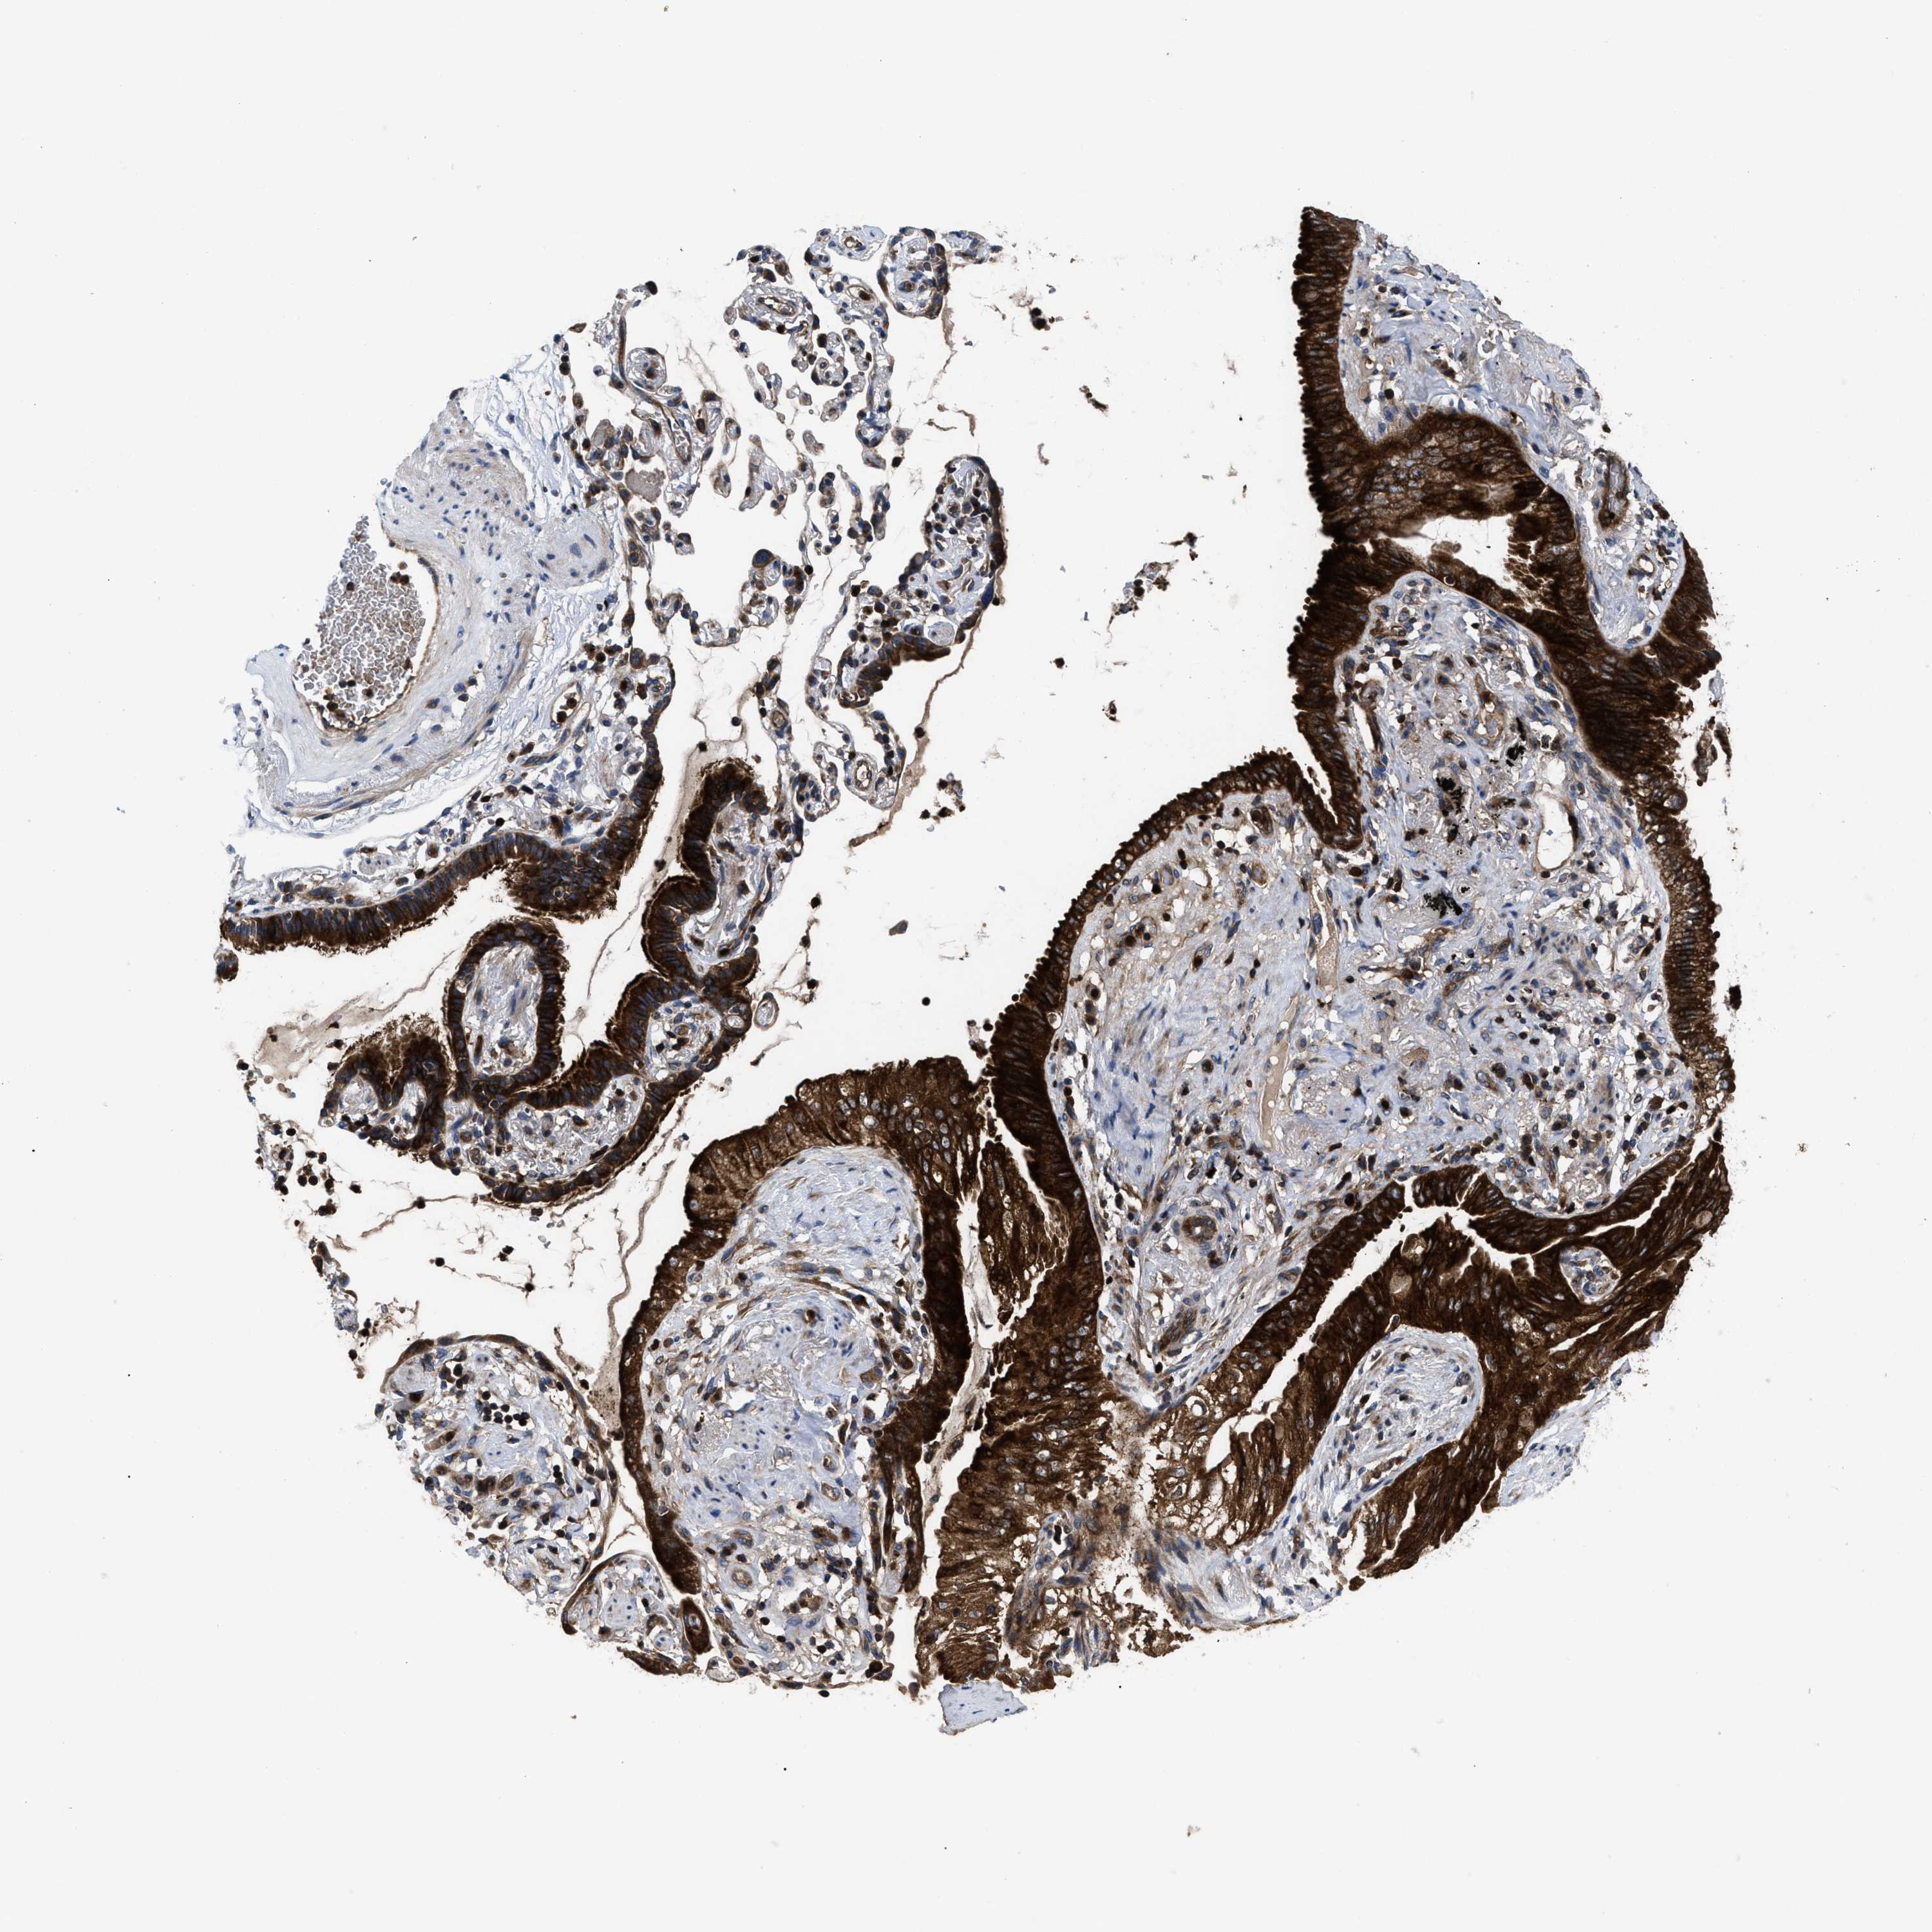

LUNG SQUAMOUS CELL CARCINOMA (TCGA) - Interactive survival scatter ploti

The Survival Scatter plot shows the clinical status (i.e. dead or alive) for all individuals in the patient cohort, based on the same data that underlies the corresponding Kaplan-Meier plots. Patients that are alive at last time for follow-up are shown in blue and patients who have died during the study are shown in red.

The x-axis shows the expression levels (FPKM) of the investigated gene in the tumor tissue at the time of diagnosis. The y-axis shows the follow-up time after diagnosis (years). Both axes are complimented with kernel density curves demonstrating the data density over the axes. The top density plot shows the expression levels (FPKM) distribution among dead (red) and alive patients (blue). The right density plot shows the data density of the survived years of dead patients with high and low expression levels respectively, stratified using the cutoff indicated by the vertical dashed line through the Survival Scatter plot. This cutoff is automatically defined based on the FPKM cutoff that minimizes the p-score. The cutoff can be changed by dragging the vertical line or by entering a cutoff value in the square labeled "Current cut-off".

Under the Survival Scatter plot the p-score landscape (black curve; left axis) is shown together with dead median separation (red curve; right axis). Dead median separation is the difference in median mRNA expression between patients who have died with high and low expression, respectively. It is calculated as follows: median FPKM expression of dead patients with high expression - median FPKM expression of dead patients with low expression. This is intended to aid the user in visually exploring custom cutoffs and the associated p-scores and dead median separation.

Individual patient data is displayed and can be filtered by clicking on one or more of the category buttons on the top of the page. Categories describing expression level and patient information include: high, low, alive, dead, female, male and tumor stages. The scale of the x-axis can be toggled between linear and log-scale by clicking on the "x log" button. Mouse-over function shows TCGA ID, patient information and mRNA expression (FPKM) for each patient.

& Survival analysisi

Kaplan-Meier plots summarize results from analysis of correlation between mRNA expression level and patient survival. Patients were divided based on level of expression into one of the two groups "low" (under cut off) or "high" (over cut off). X-axis shows time for survival (years) and y-axis shows the probability of survival, where 1.0 corresponds to 100 percent.

YBEY is not prognostic in Lung Squamous Cell Carcinoma (TCGA)

Stage:

Best expression cut offi

Based on the FPKM value of each gene, patients were classified into two groups and association between prognosis (survival) and gene expression (FPKM) was examined. The best expression cut-off refers the FPKM value that yields maximal difference with regard to survival between the two groups at the lowest log-rank P-value. Best expression cut-off was selected based on survival analysis .

When clicking on this number, the vertical dashed line indicating cut-off, the interactive survival plot, and the Kaplan-Meier curve will be adjusted to show results based on the best expression cut-off.

: 9.45

P scorei

Log-rank P value for Kaplan-Meier plot showing results from analysis of correlation between mRNA expression level and patient survival.

N/A

TCGA RNA samplesi

RNA-seq data is reported as average FPKM (number Fragments Per Kilobase of exon per Million reads), generated by the The Cancer Genome Atlas (TCGA) .

Normal distribution across the dataset is visualized with box plots, shown as median and 25th and 75th percentiles. Points are displayed as outliers if they are above or below 1.5 times the interquartile range. FPKM values of the individual samples are presented next to the box plot.

Average pTPM 12.5

Number of samples 489